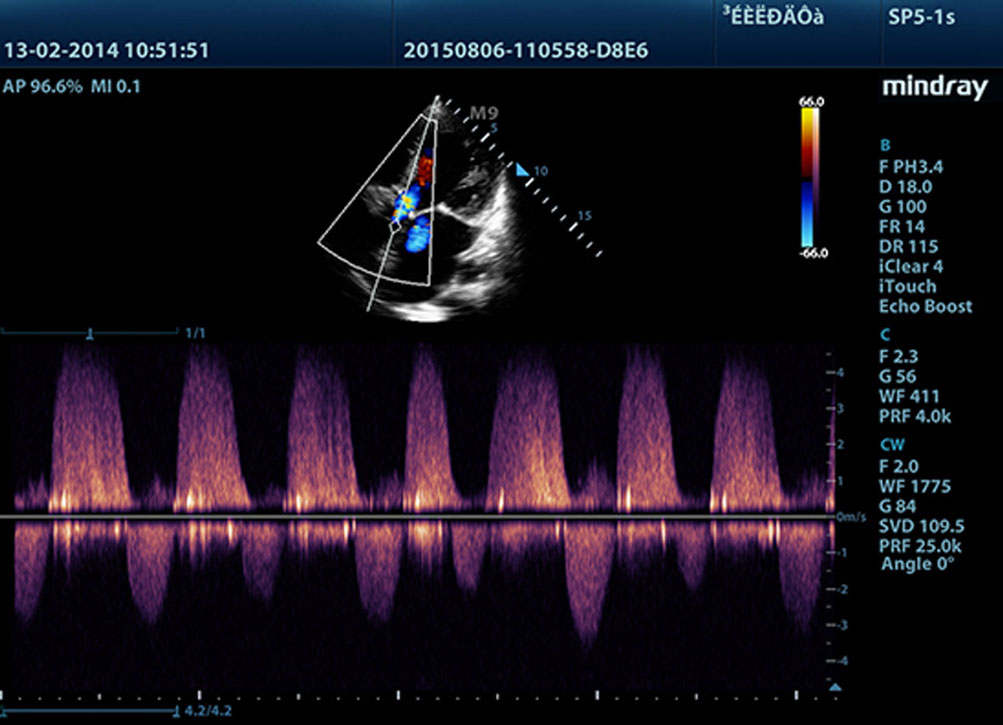

Proporcionando imĂĄgenes mĂĄs nĂtidas, todas las sondas compatibles con el M9 vienen equipadas con la tecnologĂa de transductor 3T Ășnica de Mindray. Mejorado con el a?adido de la tecnologĂa de cristal Ășnico, el M9 ofrece una mejor penetraciĂłn y flujo dinĂĄmico de color, especialmente durante escaneado de pacientes difĂciles.

La tecnologĂa Ășnica de procesamiento de se?ales adaptativa de Mindray con detecciĂłn inteligente por eco ha sido dise?ada para utilizar la informaciĂłn nativa se?al-ruido con el fin de mejorar las se?ales de eco dĂ©biles suprimiendo al mismo tiempo el ruido y el desorden circundantes, proporcionando asĂ un brillo de imagen mĂĄs equilibrado y una visualizaciĂłn mejorada de las capas del miocardio.